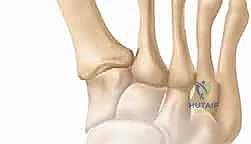

لفهم طبيعة جراحة إعادة بناء مقدمة القدم الروماتويدية، يجب أولاً فهم التشريح الدقيق لهذه المنطقة الحيوية. تتكون مقدمة القدم من خمسة عظام مشطية (Metatarsals) تتصل بسلاميات الأصابع (Phalanges) عبر المفاصل المشطية السلامية (MTP Joints). هذه المفاصل هي المسؤولة عن تحمل وزن الجسم أثناء مرحلة الدفع في دورة المشي.

في الحالة الطبيعية، تعمل الأربطة والأوتار بتناغم للحفاظ على استقامة الأصابع وتوزيع الضغط بالتساوي. ولكن، عندما يهاجم الروماتويد هذه المفاصل، يحدث التالي: